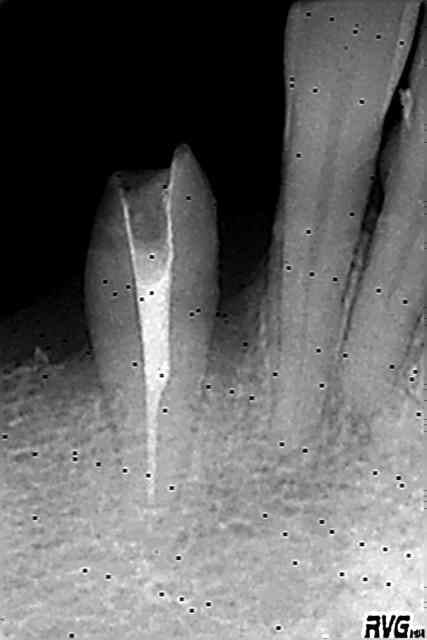

La première Rx. date de 14 ans. Rx. de controle après reprise de traitement.

43 Taille avec biseau périphérique, pilier de bridge de 43 à 46.